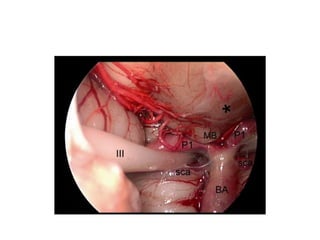

a,b Intraoperative image of the fenestration of deep cystic membrane using different microsurgical

instruments (forceps and scissors). Asterisks posterior communicating artery and anterior choroidal

artery. c Fenestration of the cisternal layer (cross Liliequist’s membrane). d Intraoperative picture at the end

of the procedure